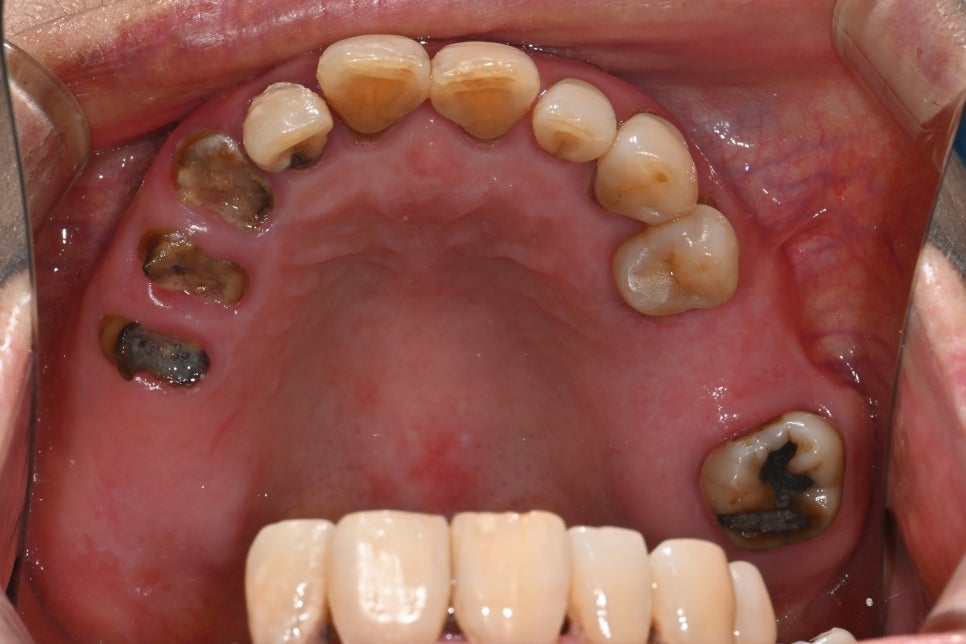

Condition at the Time of Visit

The patient had delayed dental care for more than 30 years,

and as a result, overall tooth wear, tooth loss, and gum inflammation

had developed together.

In particular, almost all molars were missing,

so chewing function had been lost,

and the remaining teeth were severely worn,

making it difficult to maintain the bite.

Food was repeatedly trapped between the gums,

causing recurring inflammation and odor,

and even everyday meals were very uncomfortable.